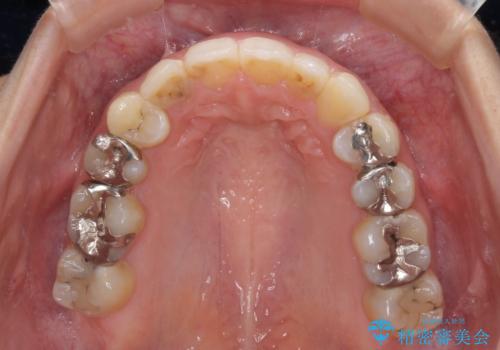

- 中学生の時に矯正治療をしたものの、後戻りを気にして来院された患者様です。

骨格的に下顎が右側に変位しているため、左右の咬み合わせを理想的なものに改善することはできませんが、インビザラインにて歯列を整えることとしました。

骨格的なズレによる左右差は改善できませんでしたが、上下の正中を極力合わせるようにすることができました。